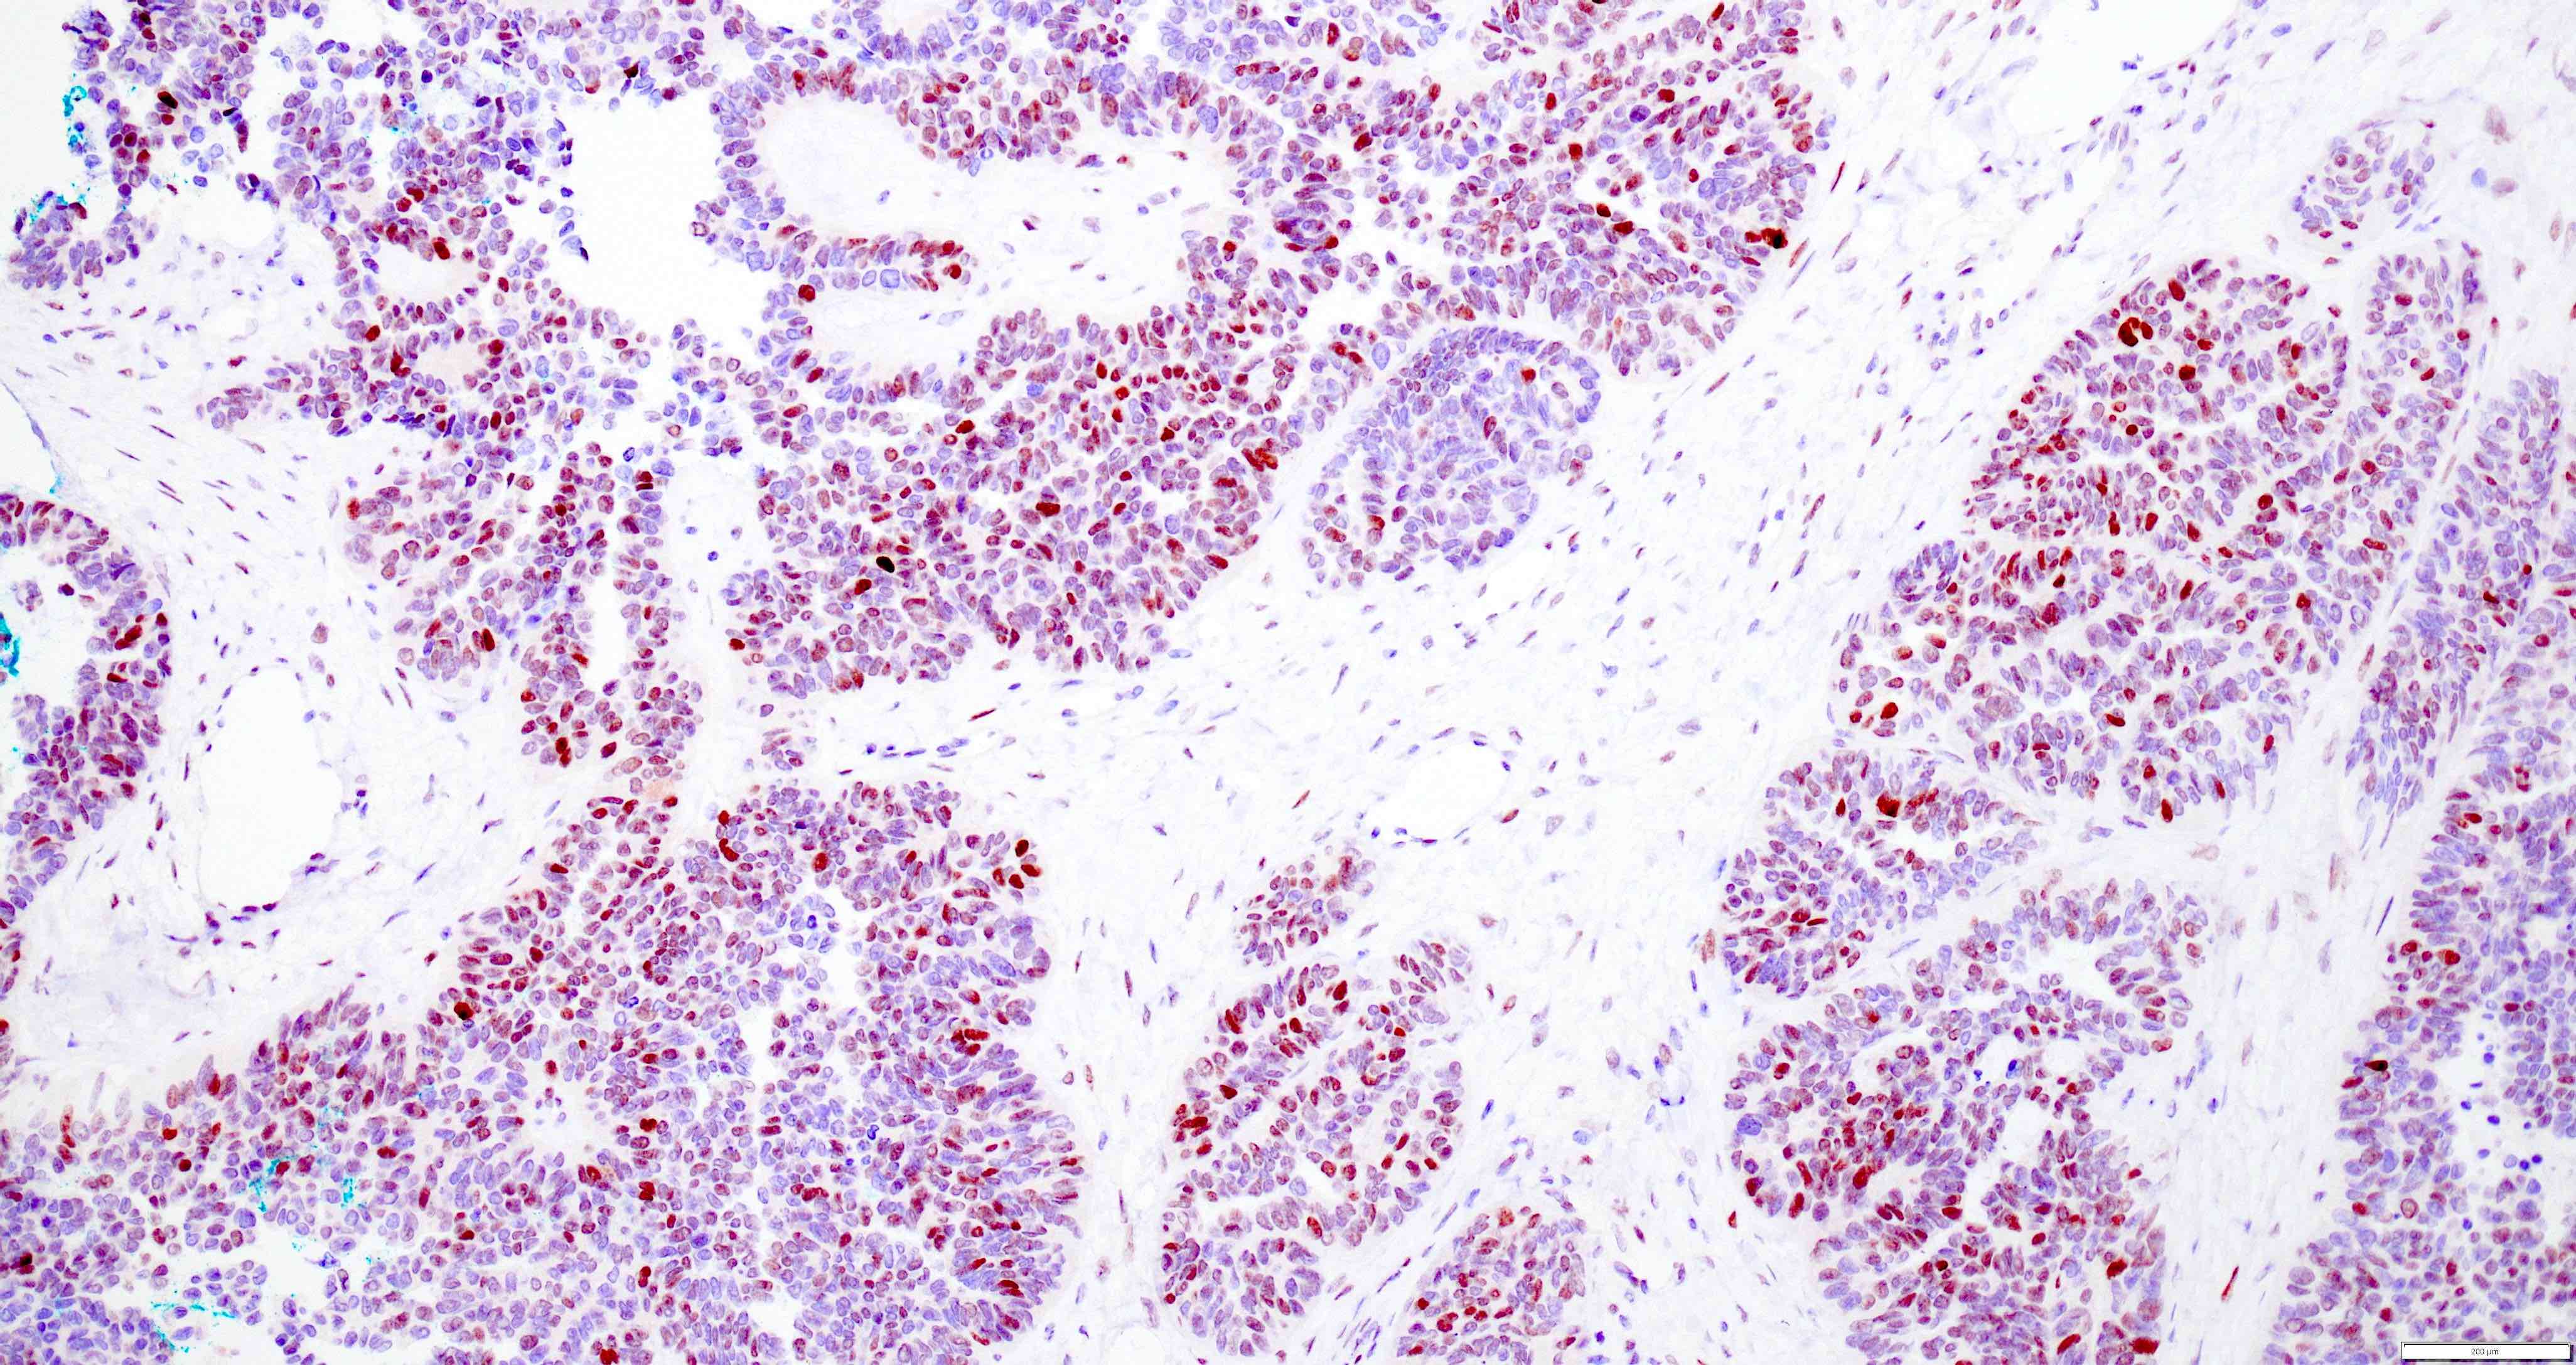

Microscopic (histologic) images

Contributed by Daniel Graham, M.D., Adele Wong, M.B., B.Ch., B.A.O. and Lucy Ma, M.D.

Positive stains

- PAX8: usually diffusely positive

- GATA3 and TTF1: focal or diffuse with inverse staining pattern described in several studies in the most recent WHO classification; cells positive for GATA3 are negative for TTF1 and vice versa (Am J Surg Pathol 2018;42:1596)

- CD10: focal and apical / luminal

- p53 wild type

- MMR proficient

Negative stains

- ER

- PR (more reliable negative marker than ER)

- Calretinin (usually negative may be focally positive)

- Comment: The tumor exhibits various growth patterns including small tubular, glandular and papillary areas. Tumor cells show diffuse immunoreactivity for PAX8 and focal immunoreactivity for GATA3 and TTF1. Despite the predominant glandular architecture and low grade appearance, the tumor is negative for ER and PR. The cervix is benign and mesonephric remnants are not identified. All these findings are most consistent with endometrial adenocarcinoma, mesonephric-like subtype.